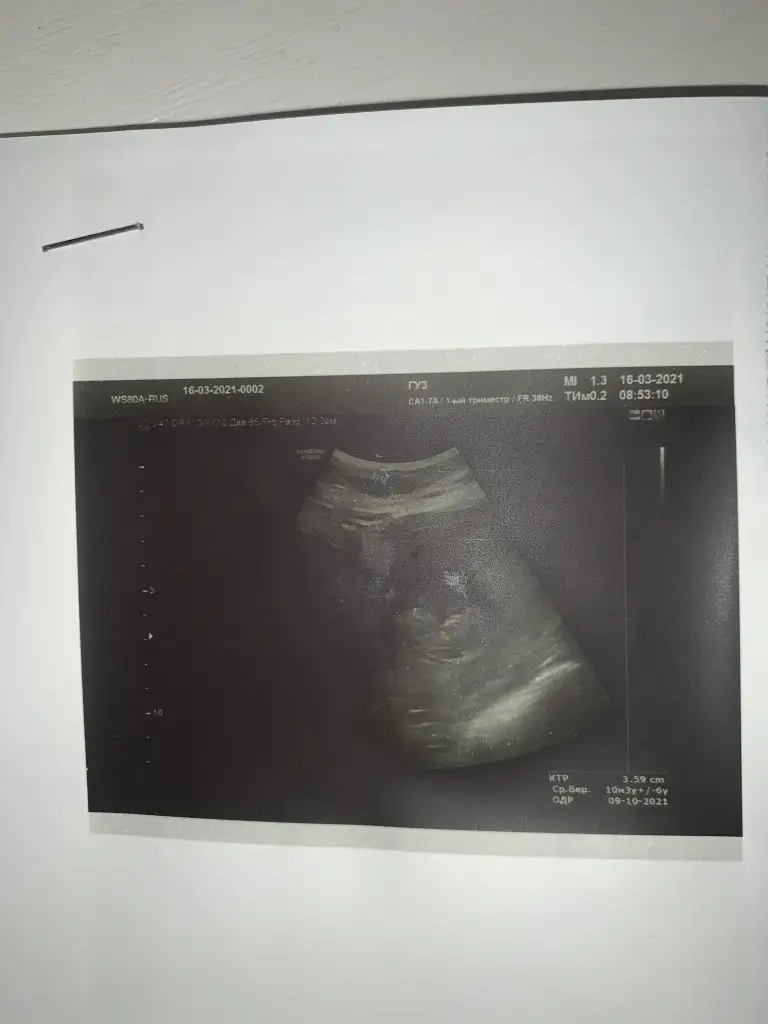

Merhaba. Rica etsem benim usmya tahmin yapar mısınız?

12+2 günlüktü burda. Karından detaylı ultrasondu.

Doktor benzetme yaptı ama kesin değil dedi.doktorla aynı olursa oyumu veririm

Kız sanki başka USG varsa paylaşın